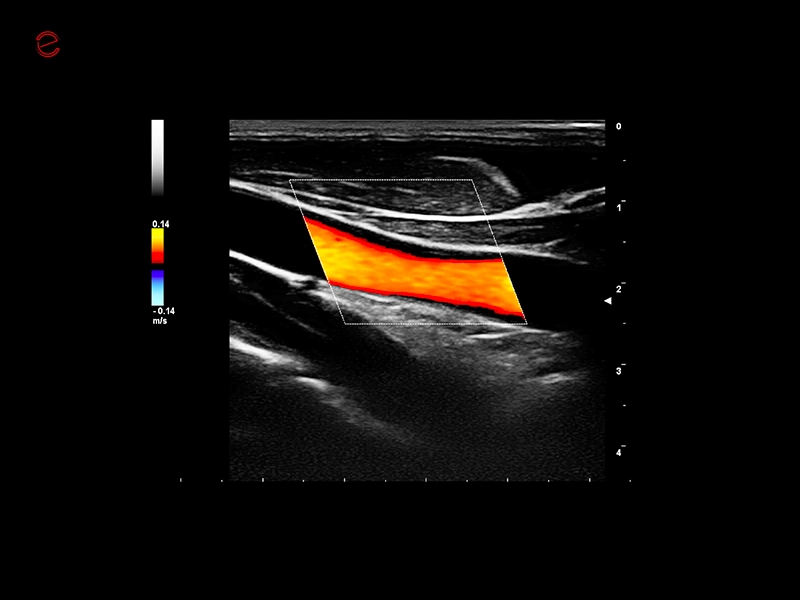

MyLab™9 Platform - QIMT Intima-media thickness quantification based on radio frequencies in real-time studies

MyLab™9 Platform - QIMT Intima-media thickness quantification based on radio frequencies in real-time studies